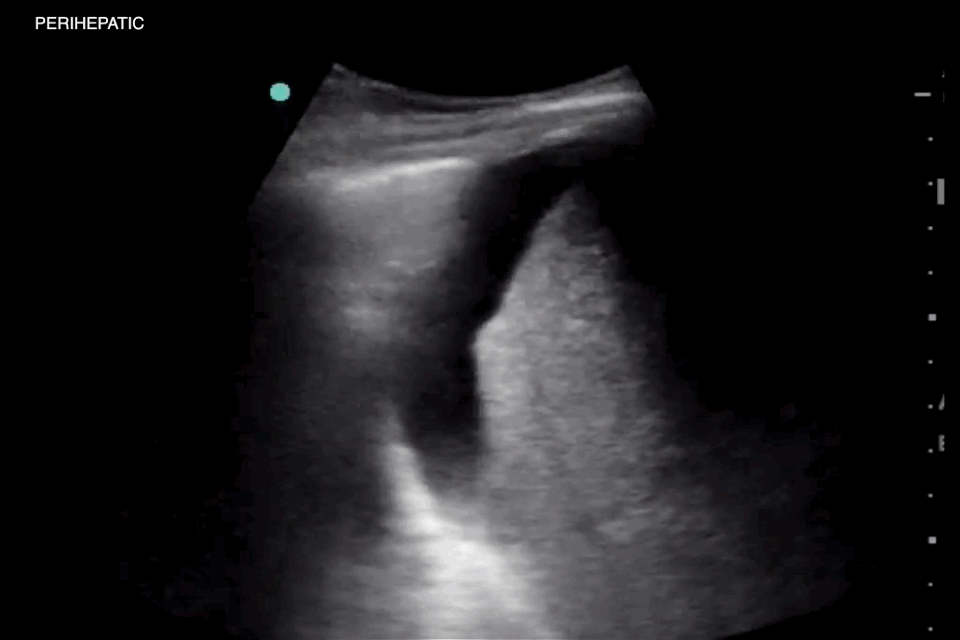

Pitfall – Gall stone